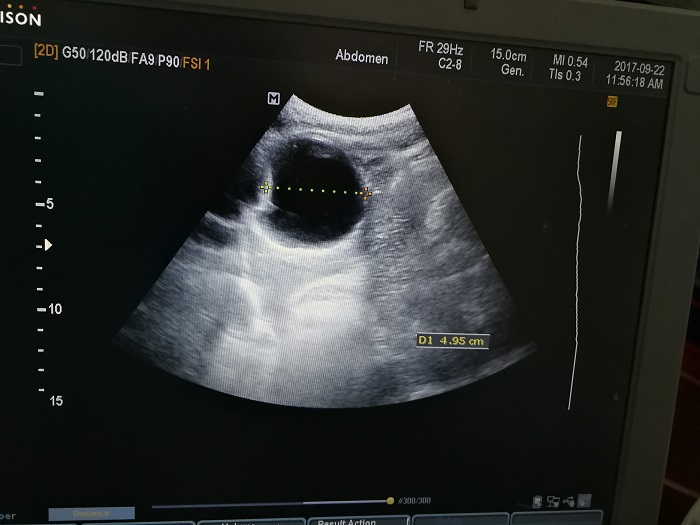

扎西(化名),男,15岁,包虫病筛查阳性,牧区孩子,家里有牦牛20头、羊200只,狗1条,牛羊自家屠宰,饮用河水。

●革吉县初级中学筛查点 · B超现场图片

除了包虫病筛查外,连续三天的学校体检我医疗队发现肾积水、肾囊肿、肾结石的学生患者较多,我们将体检到的相关脏器疾病同时间反馈给了班主任,让他们密切观察病情,及时通知家长。刘冬梅医生建议,学校要组织学生多饮水,同时多加观察本地水质情况。

本次筛查,革吉县初级中学共筛查学生498例,阳性3例,疑似2例。